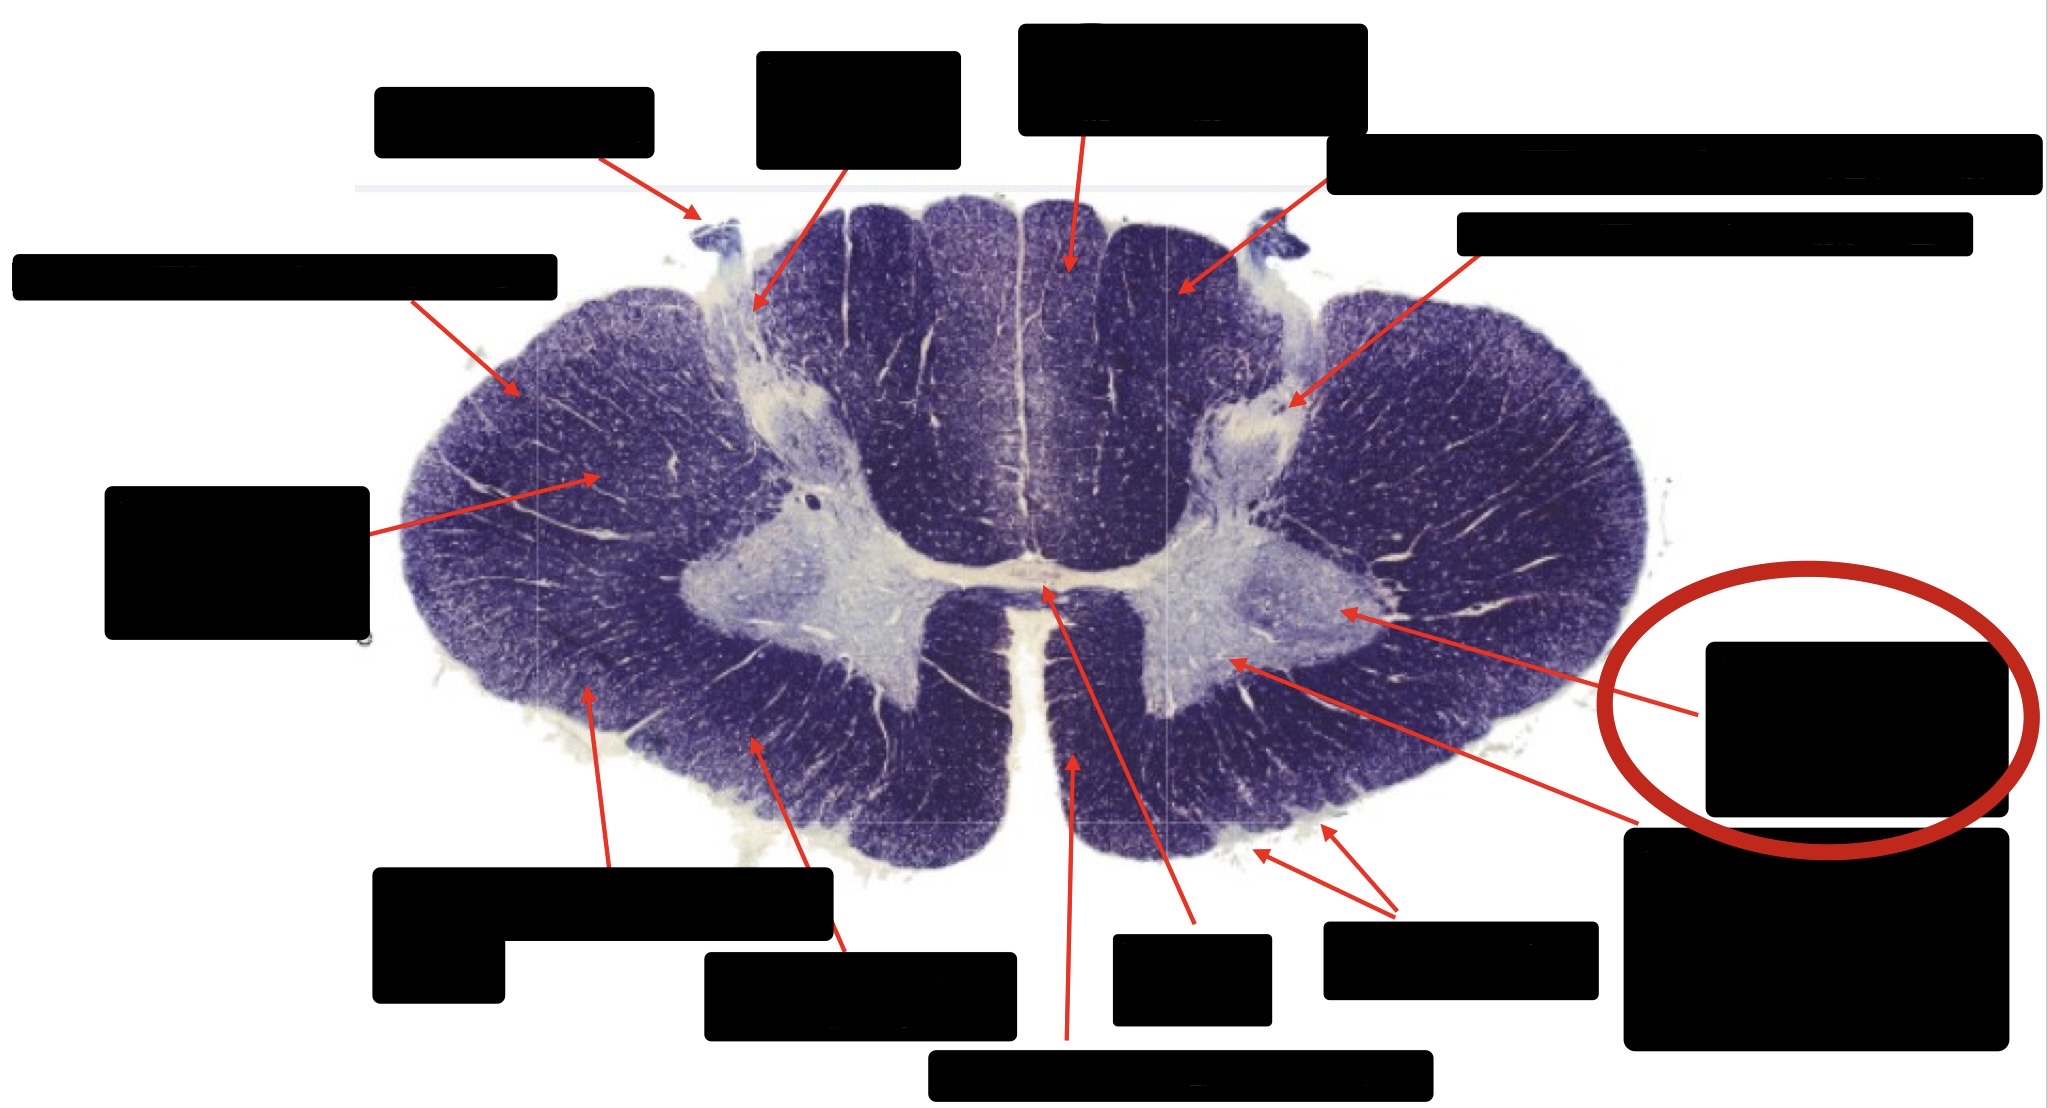

Central Canal

Posterior Column (Fasciculus Gracilis)

Large Fiber Entry Zone

Lissaeur’s Tract & Small Fiber Entry Zone

Substantia Gelatinosa

Lateral Corticospinal Tract

Ventral Root Fibers

Anterior Horn Motor Neurons

Anterior Medial Fissure

Dorsal Rootlet

Posterior Spinocerebellar Tract

Anterior Spinocerebellar Tract

Spinothalmic Tract

Posterior Column (Fasciculus Cuneatus)

Anterior Horn Motor Neurons (Distal Muscles)

Anterior Horn Motor Neurons (Proximal Muscles)

Anterior Corticospinal Tract